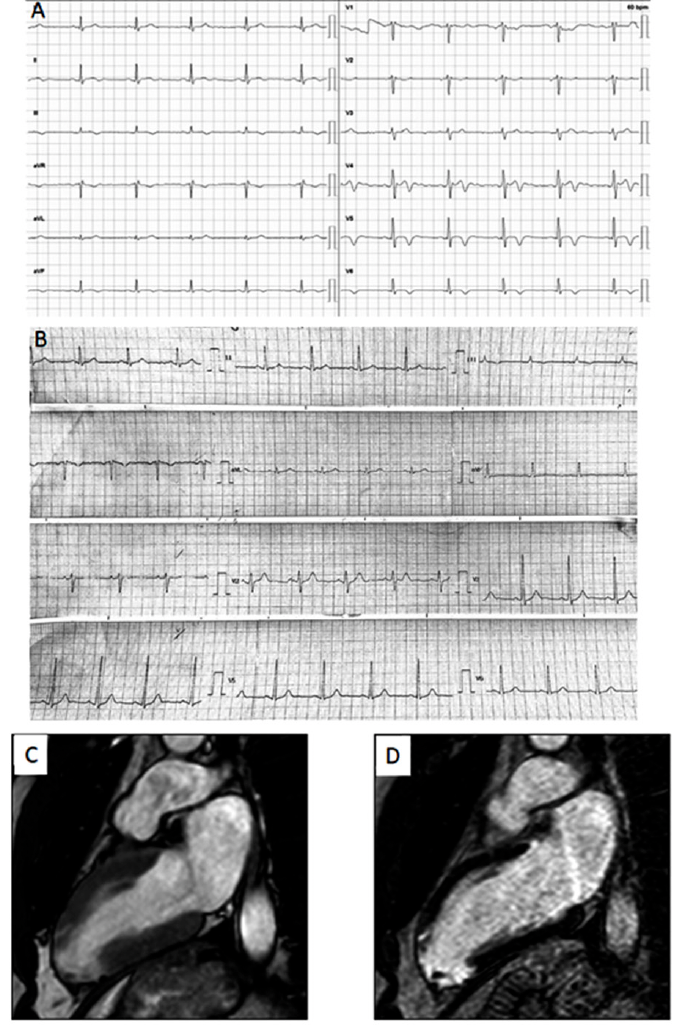

Dos casos de infarto con arterias coronarias normales en el contexto de infección aguda por coronavirus